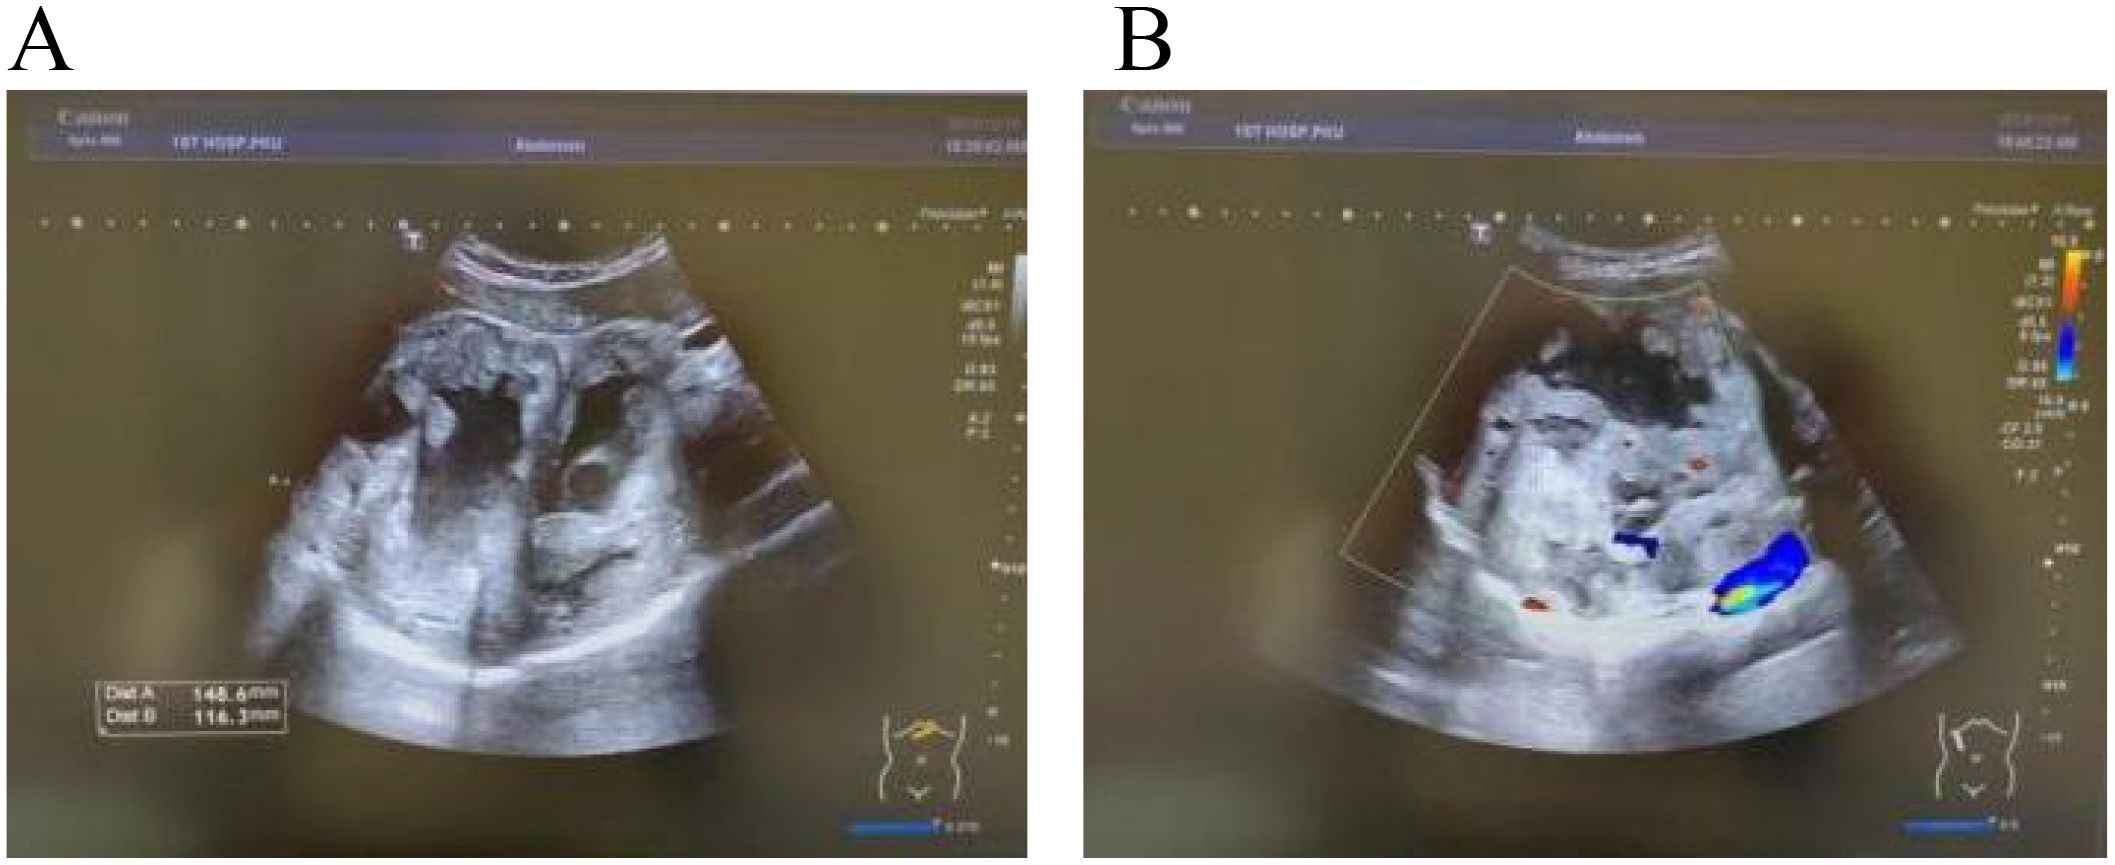

Introduction: Intrahepatic papillary neoplasm of the bile duct (IPNB) with invasive carcinoma is a rare cholangiocarcinoma with most frequent site of origin being intrahepatic bile ducts. Given its rarity and nonspecific clinical presentations, accurate diagnosis plagues clinicians to improve patient outcomes. Case presentation: We present a case of a 31-year-old male who initially exhibited fever. Routine ultrasonography and computed tomography (CT) revealed a large mass in the right liver lobe, suggesting a high likelihood of an infectious lesion. However, multidisciplinary discussion offered a variety of possible scenarios. The patient subsequently underwent an extend right hepatectomy (ERH), and histopathological examination suggested a intrahepatic IPNB with invasive adenocarcinoma. Clinical discussion: The diagnosis and management of IPNB remain challenging, particularly in patients who present with atypical clinical symptoms and lack significant abnormalities in laboratory tests. Early imaging plays a critical role in guiding the diagnostic process. However, a comprehensive diagnostic speculations, clinical expertise, and even invasive detections are essential for establishing a definitive diagnosis and determining the appropriate treatment strategy. Given the potential to invasive carcinoma, early detection and resection are vital to improve prognosis.